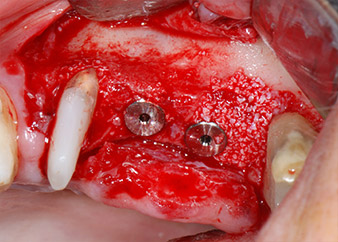

Имплантологичното ложе е подготвено в позиции 25 и 26 с ротиращи инструменти, използвайки обратен наконечник 20:1 с усъвършенстван и мощен имплантологичен мотор (Implantmed, W&H) (Фиг. 8).

Имплантите (Restore, Keystone Dental, диаметър 3,75 mm, дължина 8.0 mm) са поставени с имплантологичен мотор

(Фиг. 11 и 12).